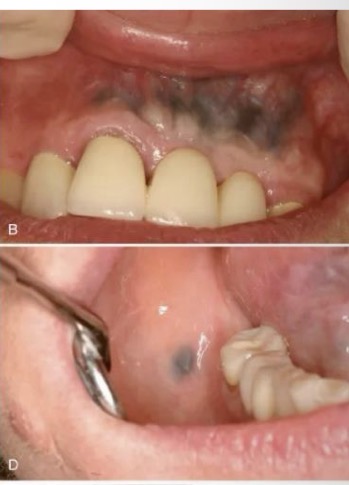

CHẨN ĐOÁN?

NHIỄM SẮC DO NHIỄM ĐỘC CHÌ Ở VIỀN NƯỚU

CHẨN ĐOÁN

NHIỄM SẮC AMALGAM

CHẨN ĐOÁN .?